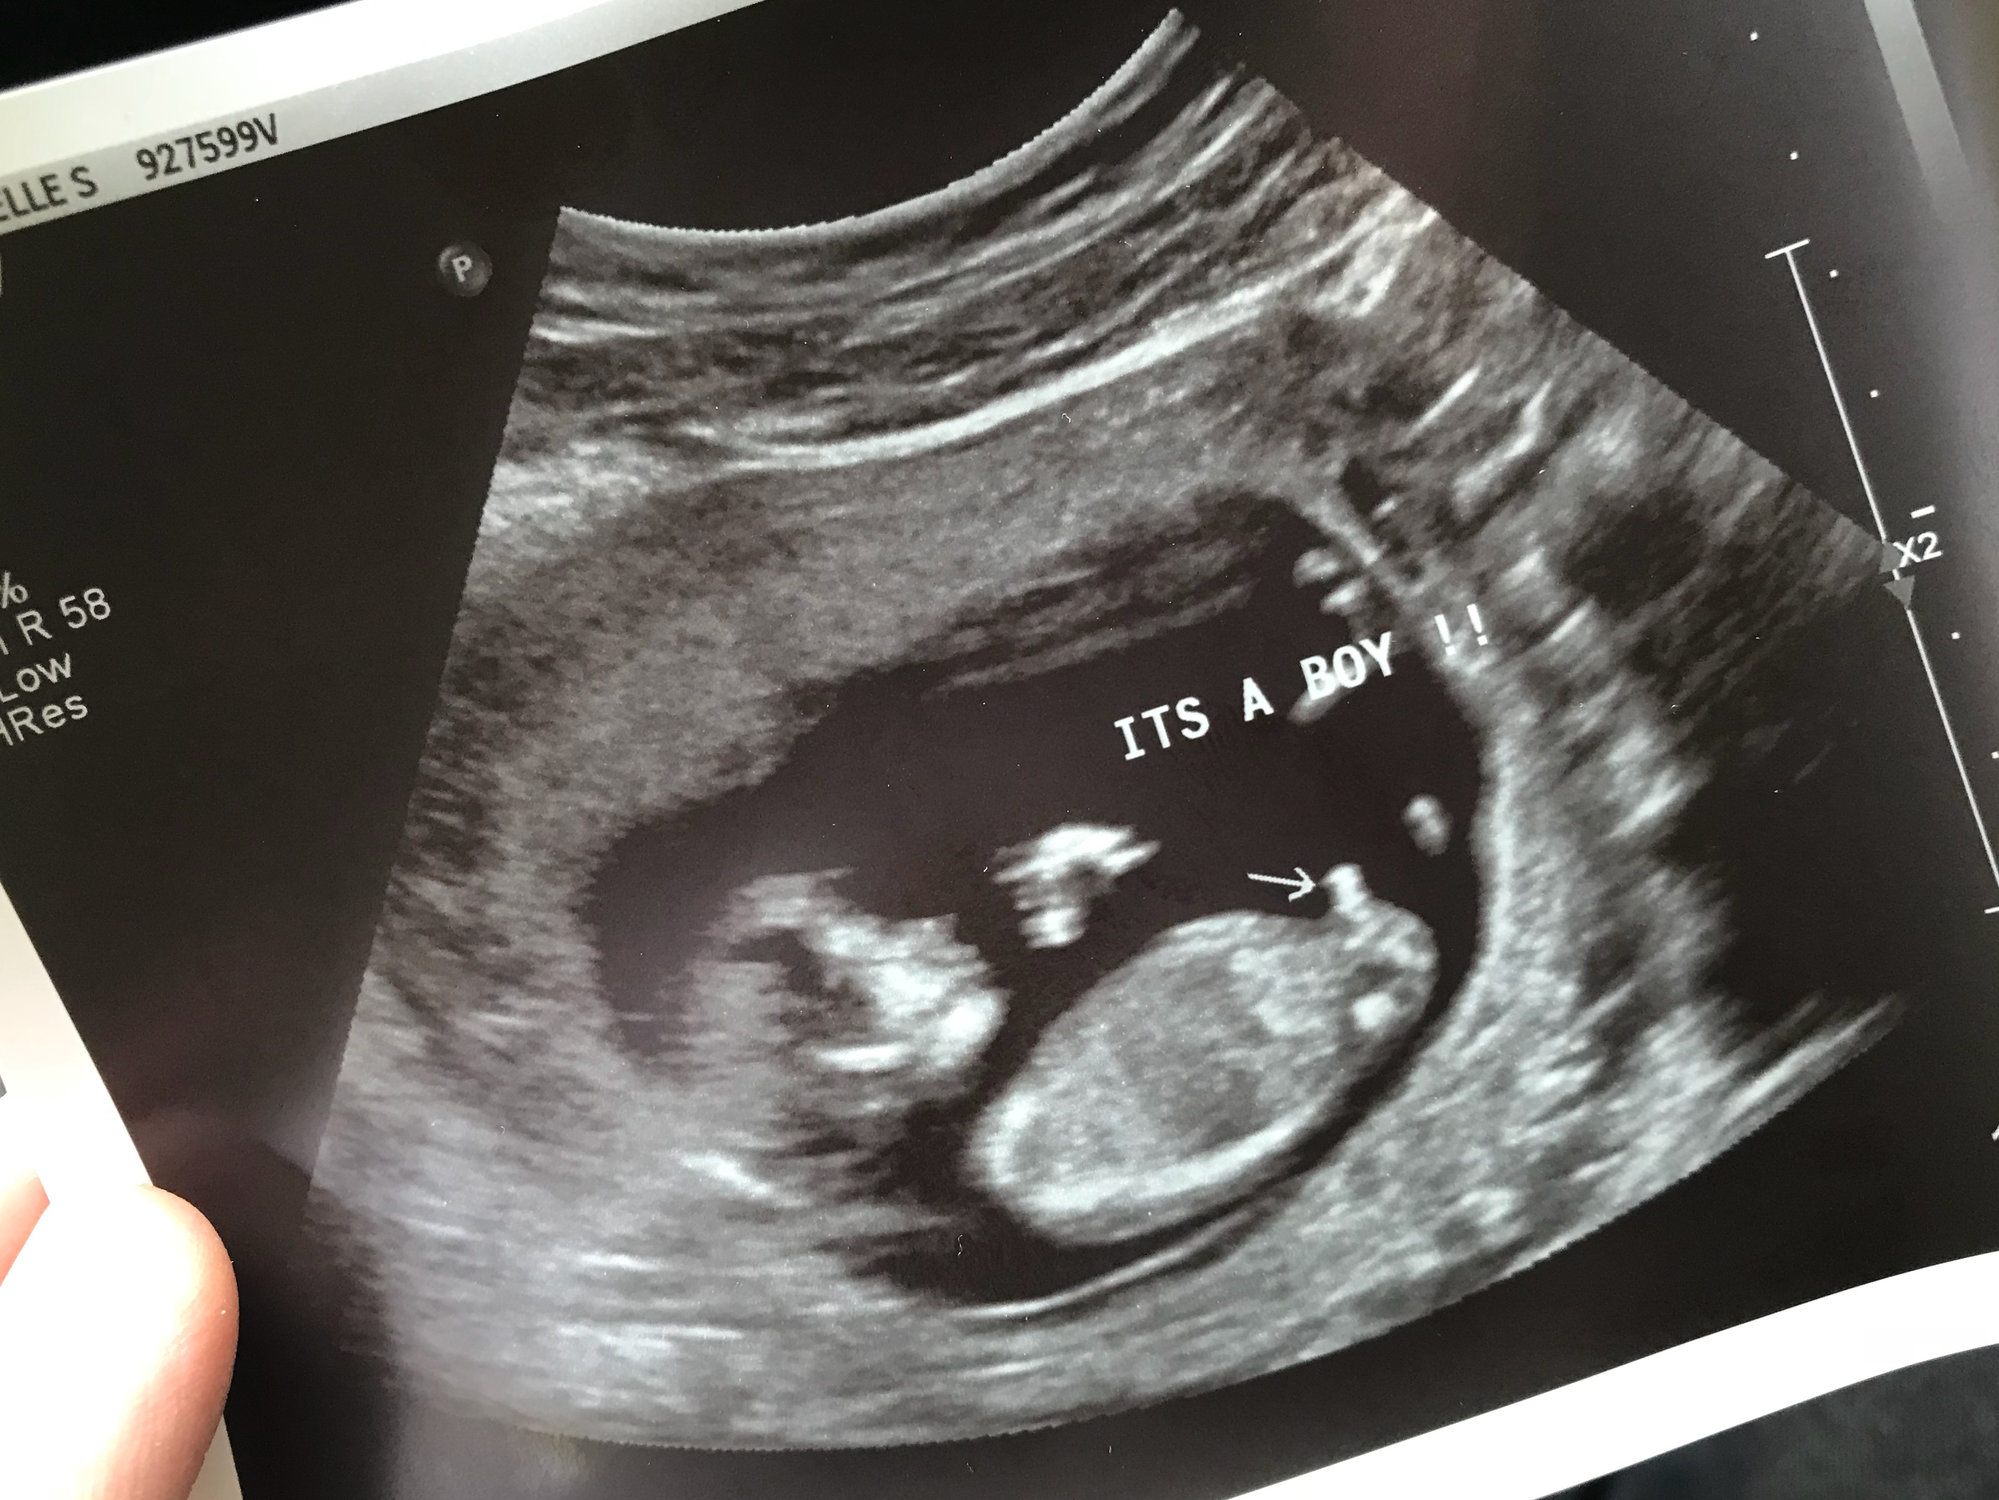

All about the SEX (It's a BOY/GIRL!)

Let's see how the numbers shake out. Go ahead and vote when you find out! If you're team green, come back and vote when your baby gets here.

All about the SEX (It's a BOY/GIRL!) 96 votes

Boy

51% 49 votes

Girl

44% 43 votes